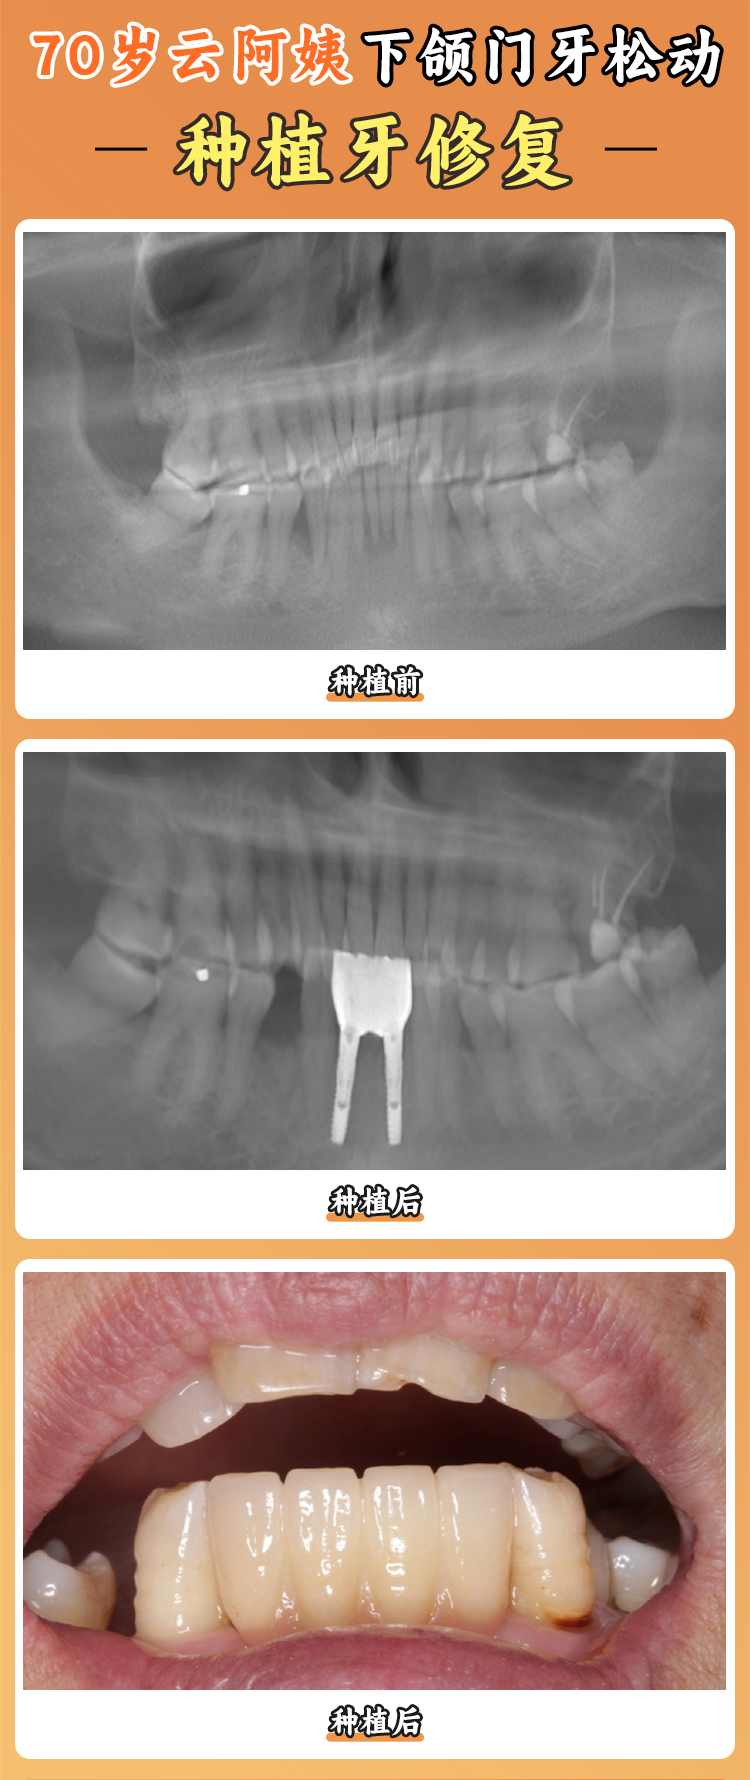

上海瑞伢美口腔提供齊全的口腔診療服務(wù),其中多個(gè)特色項(xiàng)目受到患者好評(píng)。數(shù)字化種植牙采用精良的3D導(dǎo)板種植技術(shù),通過(guò)CBCT精細(xì)掃描,計(jì)算機(jī)輔助設(shè)計(jì)種植方案,實(shí)現(xiàn)微創(chuàng)、精細(xì)、快速的種植牙手術(shù)。特別適合單顆牙缺失、多顆牙缺失甚至全口無(wú)牙的患者。這種技術(shù)可以將誤差控制在0.1毫米內(nèi),大大提高了種植牙的成功幾率。劉先生是全口牙缺失患者,在上海瑞伢美口腔接受了數(shù)字化種植牙手術(shù),術(shù)后修復(fù)快,種植牙的成效也非常好,現(xiàn)在他又能正常享受美食了。